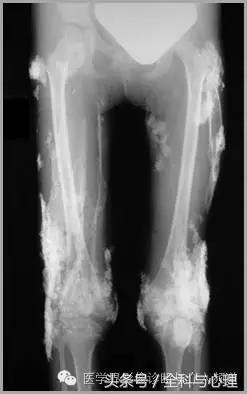

1、全身性钙质沉着症:皮肤、皮下或深部结缔组织钙化,与多种代谢紊乱及胶原血管病变有关,如皮肌炎,看起来像异位骨化,但没有真正的骨形成。开始为浅表的结节状或斑块状钙化,逐渐向更深的组织发展,表现为关节周围大片状钙化灶。

皮肌炎